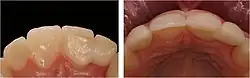

Die Klebebrücke sollte im Oberkiefer-Frontzahnbereich und im Seitenzahnbereich nicht mehr als einen Zahn ersetzen. Im Unterkiefer-Frontzahnbereich sollten maximal die vier Schneidezähne ersetzt werden und dies nur dann, wenn in dieser Region ein gerader Kieferverlauf besteht.

Eine wichtige Voraussetzung für die Versorgung mit Klebebrücken ist die relative Kariesfreiheit der Pfeilerzähne und ein ausreichender Zahnschmelz, der beim Klebevorgang erforderlich ist.[1] Kleinere Füllungen in den Pfeilerzähnen können belassen werden, sollten aber vor dem Kleben des Zahnersatzes speziell behandelt (konditioniert) werden.